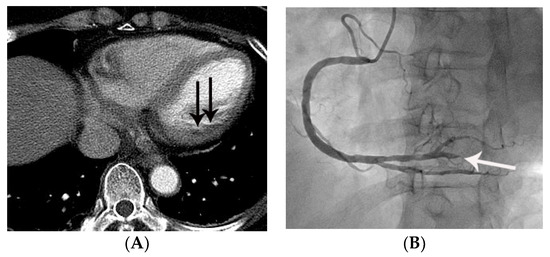

Figure 4.

False negative diagnosis of acute myocardial infarction on non-gated chest CT in a 67-year-old female with a small acute myocardial infarction. (A) Equivocal MPD (CT score of 1 for myocardial perfusion defect (MPD)) (arrow) was noted in the basal lateral segment of the left ventricle on an axial image. (B) Subsequent coronary angiography showed total occlusion (arrow) of the posterolateral branch of the right coronary artery, suggesting a culprit lesion. Note that it was difficult to differentiate true MPD from artifacts in this case.

Figure 5.

False positive myocardial perfusion defect (MPD) in a 55-year-old female with acute chest pain. Focal low attenuation (arrow) in the left ventricular apex was noted on an axial CT image. The lesion was given a CT score of 2 for MPD. However, serial ECG and serum cardiac troponin were normal, and her final diagnosis was reflux esophagitis.